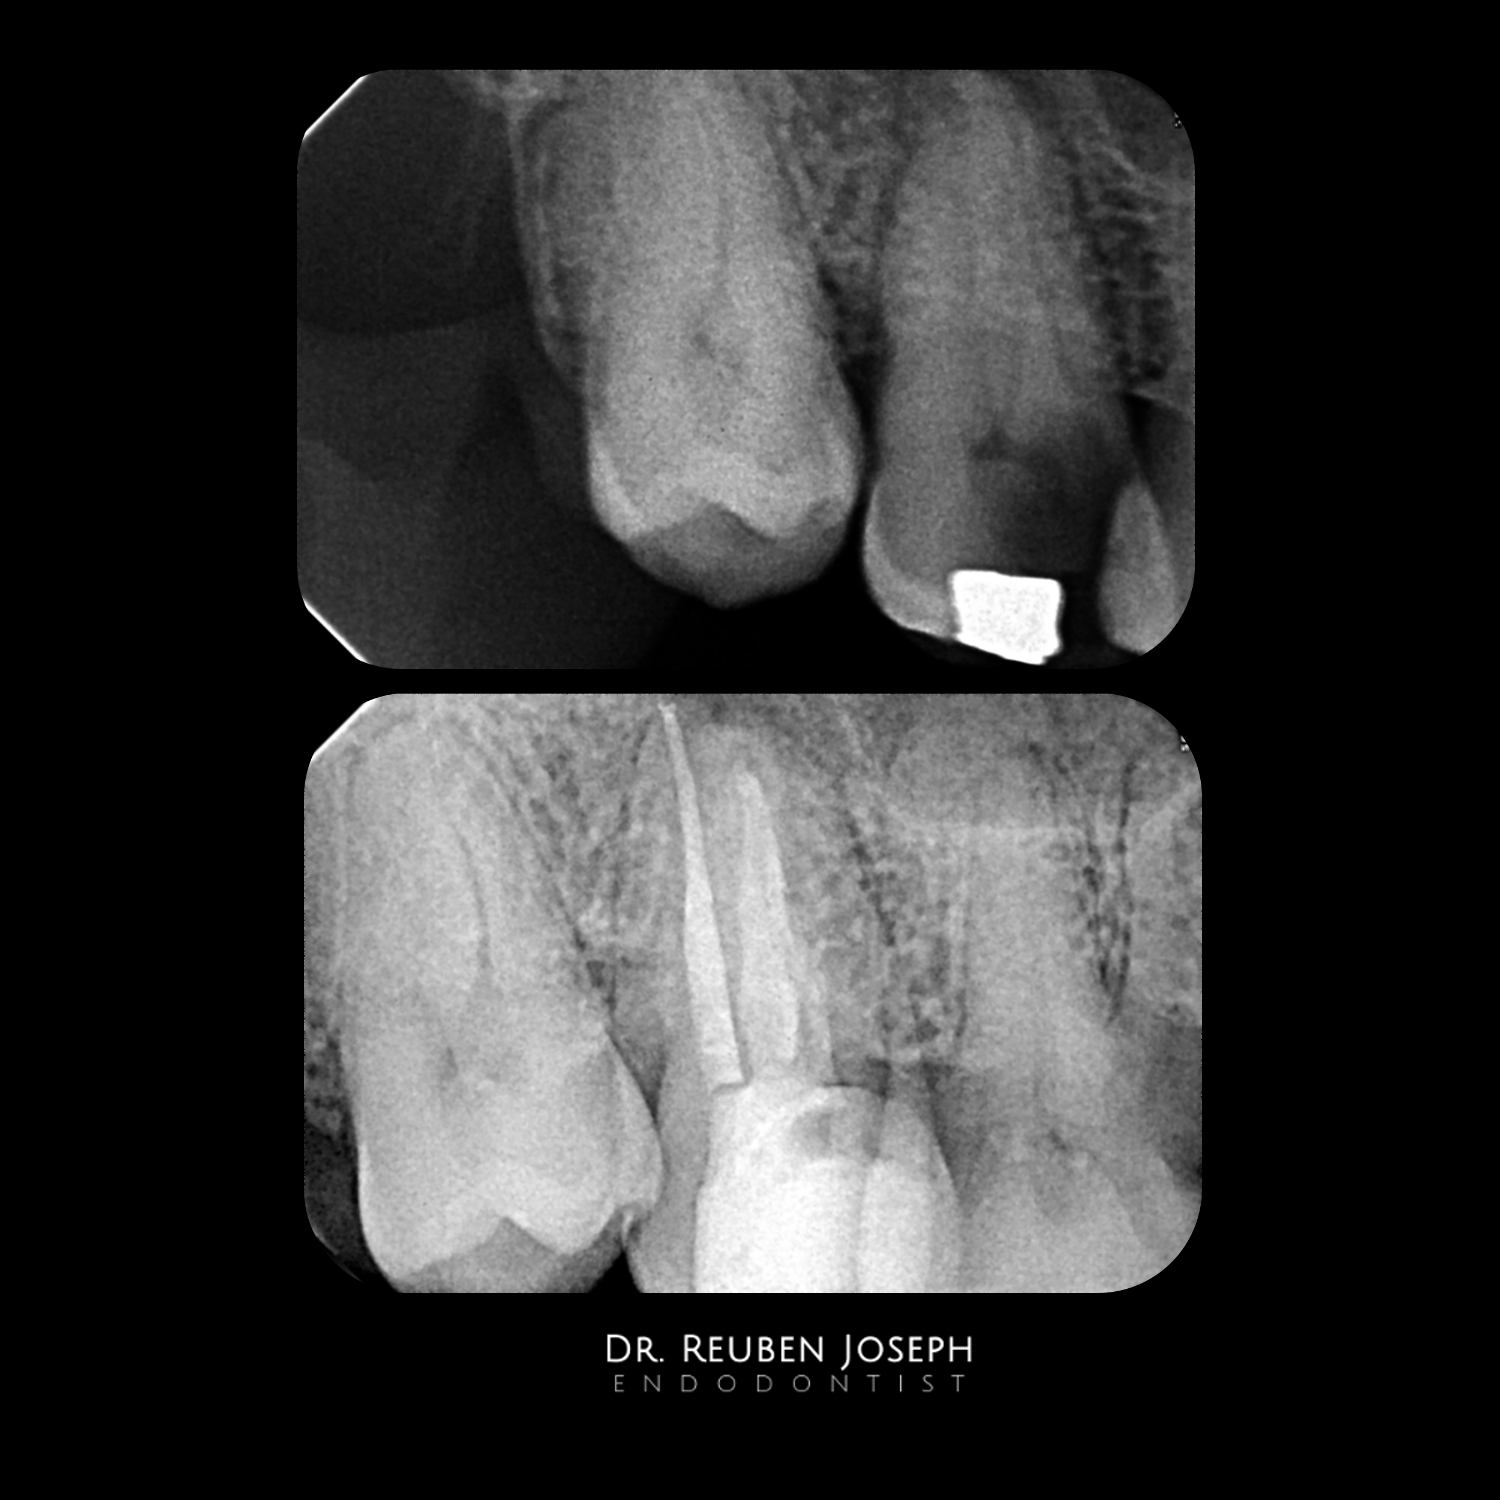

This one had Significantly large irregular canals. Palatal canal obturated with a squirt to get a 3-D fill and the buccal canal with a large POE obturated with MTA at the apical 3rd and back-filled with GP. Done in 2-visits.